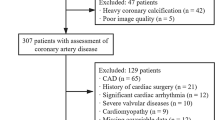

The study subjects were all patients treated at Changzhou No. 2 People's Hospital affiliated with Nanjing Medical University from September 2019 to September 2021. We retrospectively included patients with clinically suspected CAD in our institution who underwent CCTA and echocardiography followed by invasive coronary angiography (ICA) within 6 months. Exclusion criteria included the following: (a) history of coronary myocardial infarction and cardiac surgery; (b) anatomical variation of the heart or coronary artery; (c) diseases that seriously affect heart function, such as heart space–occupying lesions, cardiomyopathy, or severe heart valve disease; (d) family history of CAD; and (e) failure to reconstruct images (Fig. 1).

Initially, 197 participants with clinically suspected CAD were included. According to strict exclusion criteria, 159 patients (mean age, 64.55 ± 10.64 years; range, 43–89 years) were finally enrolled in this study (Fig. 1), including 104 men (mean age, 62.03 ± 10.58 years; range, 43–89 years) and 55 women (mean age, 69.33 ± 9.05 years; range, 51–85 years). Other baseline characteristics are shown in Table 2.